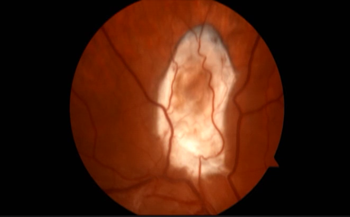

还有一位患者 , 眼睛里进了猪肉绦虫 , 病例堪称美国前所未见 , 但他却不着急就医 。

卡车司机Jake起初发现眼部不适 , 但他觉得是小问题 , 随后眼睛有明显充血 , 他知道问题大了 , 但依然不想就医 。

他的视力直线下降 , 照镜子看不清自己 , 仿佛隔着一层蜡纸 , 痛起来像是被拳打 , 又像是被刀扎 , 极为痛苦 。

医生在检查后 , 也被他的情况惊呆了 , 因为在Jake的眼睛里 , 他发现了一只猪肉绦虫 。 虽然罕见 , 但其实这种寄生虫有时会从肠道移动 , 方向有两个选择:脑部或者是眼部 。

而Jake当时的情况已经相当糟糕 , 可能连眼球都保不住 。

本文图片

不过 , 他还算是幸运的 , 手术进行的很顺利 , 经历过痛苦的他 , 又能开车了 。